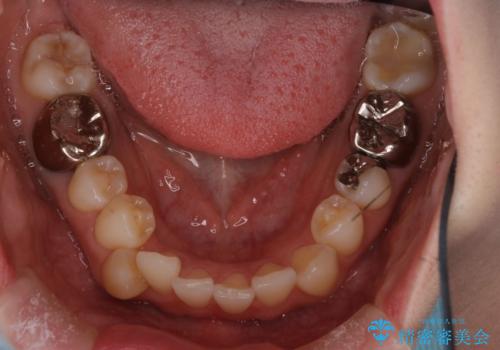

- 前歯の翼状捻転の改善を希望してこられた患者様です。

下顎の叢生はインビザラインで解決することがきましたが、上顎の捻転が完全には改善できなかったため、上顎は途中からワイヤーを用いて治療を行っています。